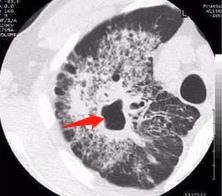

1.“树芽征”和小叶中心结节:

结核引起小气道炎症,形态类似小树芽

小树芽